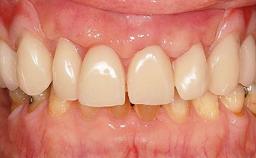

In this video Dr. Legg will demonstrate the process of utilising fully guided surgery as well as reconstruction to provide immediate full arch rehabilitation. A 56-year-old female with chronic adult periodontitis had previously undergone significant nonsurgical periodontal therapy. Unfortunately she had reached the stage where she was no longer happy with the appearance of her teeth and was suffering from increasing discomfort. A full workup was carried out in conjunction with a technical design team (at Createch). This included digital wax up of the proposed teeth, digital placement of the proposed implants and the design of the requisite surgical guides. The surgery was then carried out under sedation. The remaining upper teeth were removed, bone reduced where appropriate and the implants placed using a fully guided protocol. Following placement of screw retained abutments, the immediate provisional prosthesis was picked up in situ and passed to the technician for finishing before being fitted.

Esthetic Risk Assessment

Edentulous Esthetic Risk Assessment (fixed)

Facial Support Alveolar process provides adequate facial support

Labial Support Desired tooth position provides sastifactory labial support

Upper Lip Length Long upper lip (>20mm)

Buccal Corridor Wide Corridor

Smile Line No display of the Maxillary ridge at full smile

Maxillomandibular Relationship Class I